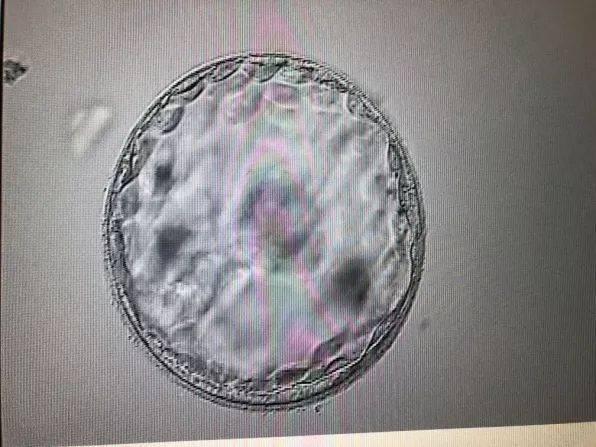

辅助生殖技术:例如人工授精(AI)、体外受精-胚胎移植(IVF-ET)等。